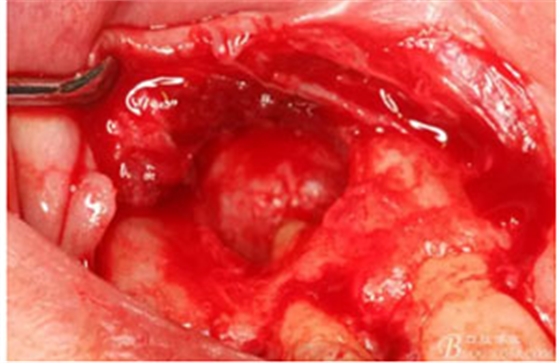

圖10。用骨膜剝離器沿著骨壁、緩慢逐漸剝離囊壁。

圖11。21囊壁被完整的剝離開來。

圖12.摘除的12根尖區(qū)的囊壁組織。

圖13.囊壁摘除后形成的骨腔,12牙根完全裸露在骨腔內(nèi)。